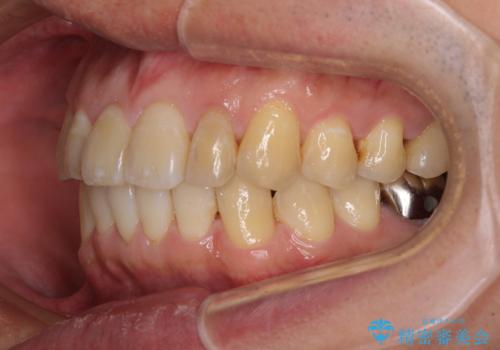

前歯のデコボコと下顎の八重歯 インビザラインによる矯正治療

- 前歯のデコボコや八重歯を気にして来院された患者様です。

インビザラインを用いて、歯列を整えることとしました。

下顎前歯は後戻りを起こしやすいため、舌側を細いワイヤーで固定し、マウスピース型リテーナーで保定を行うこととしました。